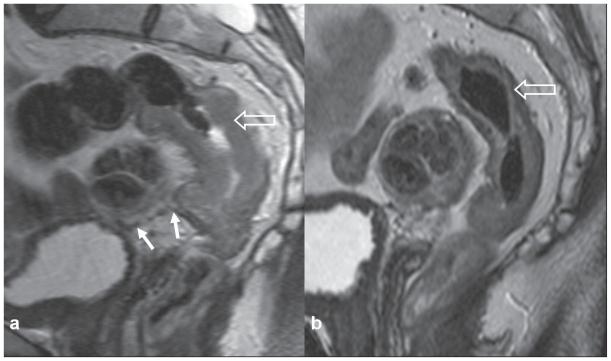

The benefit of neoadjuvant therapy for tumours above the peritoneal reflection is not clear. The purpose of this study is to demonstrate the feasibility and downstaging of treating locally advanced tumours from high rectum to distal sigmoid with preoperative chemoradiotherapy (CRT).

Seventeen patients with high rectal, rectosigmoid or distal sigmoid tumours above the peritoneal reflection received neoadjuvant CRT, selected on MRI findings indicating T4 disease or threatened circumferential resection margin. All patients were administered neoadjuvant chemotherapy, with Oxaliplatin or Mitomycin C and a Fluoropyrimidine. The pelvis received long-course CT-planned conformal RT, 45 Gy in 25 fractions, with a boost of 5.4-9 Gy in 3-5 fractions. Thirteen patients were treated with concomitant oral or intravenous Fluoropyrimidine chemotherapy.

Median follow-up was 37 months. Overall survival was 82.35% (95% Confidence Interval (CI) 54.7-93.9) and disease free survival 81.25% (95% CI 52.5-93.5). Only 1 patient suffered loco-regional relapse. Chemotherapy regimens were well tolerated, though some patients required dose reductions. Nine patients (52.9%) lowered pathologic disease AJCC stage, i.e. 'downstaged'. Six patients (35.3%) achieved complete pathological response. Clear margins were attained in all but 1 patient. Three patients were converted from cT4 to ypT3. No patient required a gap during CRT. One patient suffered a grade III acute toxicity, but no grade IV (RTOG). There were 3 grade III and 3 grade IV late toxicities (LENT-SOMA).

Locally advanced high rectal and recto-sigmoid tumours may be treated with pre-operative CRT with acceptable toxicity, impressive down-staging, and clear surgical margins.